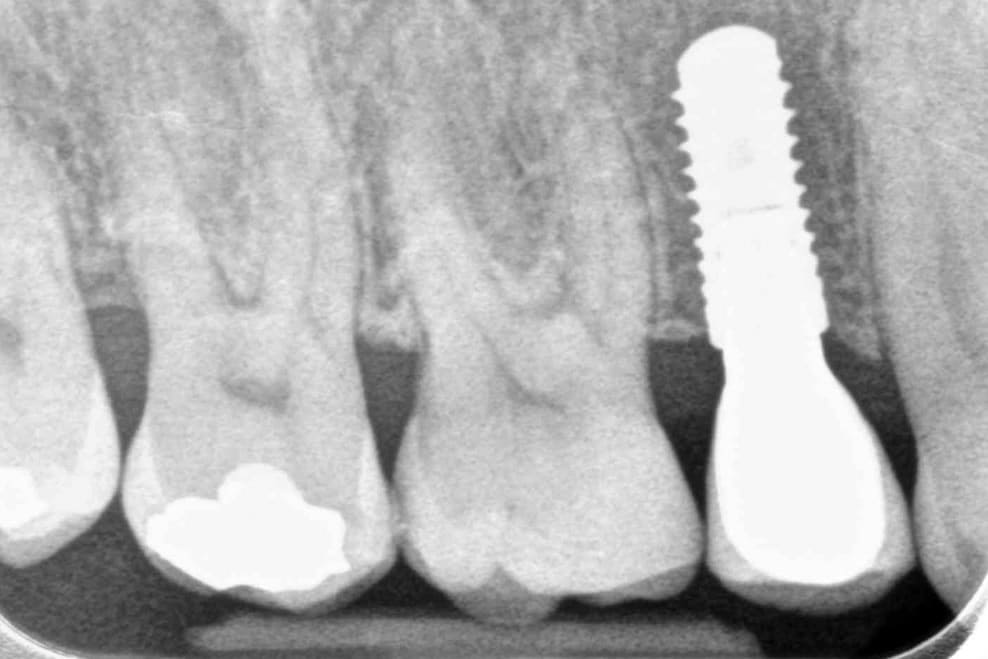

Dental implants are the best-known treatment to replace single or multiple missing teeth because they feel and behave just like natural teeth. After a while you won’t be able to tell the difference – even forgetting that they are there.

The procedure to place implants and replace a missing tooth or multiple teeth is straightforward as there is little need to treat surrounding teeth. Once a crown is placed over the implant it will appear indistinguishable from the natural teeth.

They help preserve your surrounding teeth and bone